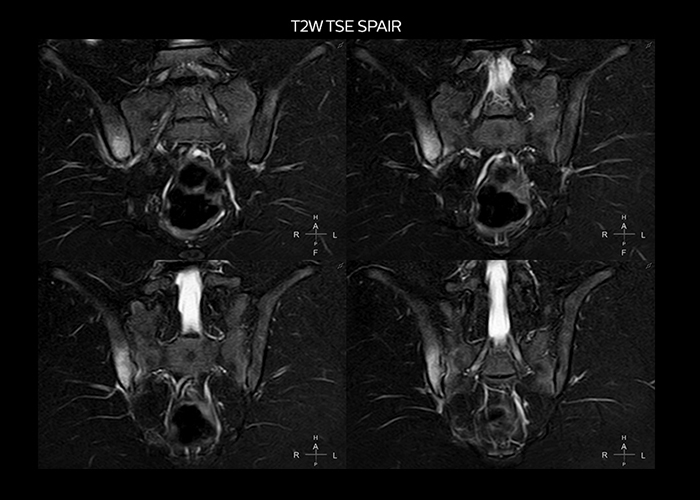

“To avoid coil changes we plan examinations of similar anatomies back to back, such as head and spine. Multiva helps us here a lot because coils don’t need to be changed frequently. Moreover, thanks to parallel imaging technology and 16-channel HeadSpineTorso and 8-channel MSK coils we are able to achieve excellent image quality. In this way Multiva helped us to increase both image quality and productivity.”

“Neurological cases, such as brain and spine imaging, represent the largest share in our MR scanning, followed by musculoskeletal cases. In general, we use simple and basic imaging protocols. But occasionally, we use advanced techniques for problematic cases if necessary.